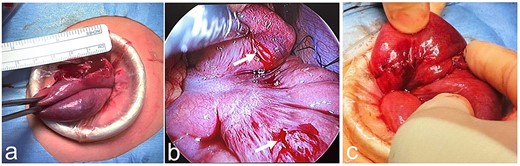

We present our experience with a 6-year-old girl who bruised her abdomen by falling while running with a thermos bottle (water bottle) hanging diagonally across her neck and left shoulder and crossing in front of her body. She went to school with a bruise on her abdomen, but 2 h after the injury she vomited and felt unwell; she was then rushed to the hospital. At the time of examination, her heart rate was 90 beats/min, her blood pressure was 110/62 mm Hg, her respiratory rate was 18 breaths per minute, her oxygen saturation was 98%, and her temperature was 36.6°C. Her abdomen was diffusely tender, but focused assessment with sonography for trauma was negative. She was kept for observation, but her symptoms did not improve. Plain abdominal CT was performed 3 h after the injury and revealed free air in the abdominal cavity, suggesting intestinal injury from blunt trauma. The whole pancreas was checked, but no obvious pancreatic injury was noted. Laboratory assessment showed a white blood cell (WBC) count of 33 200/μL, red blood cell (RBC) count of 4.82 × 106/μL, hemoglobin (Hb) of 13.1 g/dL, hematocrit (Ht) of 40.0%, a platelet count (Plts) of 436 × 103/μL, aspartate transaminase (AST) of 49 IU/L, alanine transaminase (ALT) of 13 IU/L, total bilirubin (T-Bil) of 0.4 mg/dL, and C-reactive protein (CRP) of 0.05 mg/dL (Table 1). She was transferred to our hospital 5 h after the injury. Abdominal examination on admission revealed a bruise and redness at the umbilicus (Fig. 1a), as well as diffuse signs of peritoneal irritation and muscular guarding. Upright chest X-ray showed free air in the right subdiaphragmatic region, but supine abdominal X-ray was normal (Fig. 1b and c). Laboratory assessment was repeated at our hospital and showed a WBC count of 28 960/μL, RBC count of 4.72 × 106/μL, Hb of 13.1 g/dL, Ht of 39.4%, Plts of 384 × 103/μL, AST of 48 IU/L, ALT of 12 IU/L, T-Bil of 0.5 mg/dL, amylase (AMY) of 63 IU/L, and CRP of 0.16 mg/dL (Table 1). Laparoscopic surgery was performed to assess the intestinal injury caused by blunt trauma. A transumbilical vertical incision was made, and the laparoscope was introduced. There were no apparent injuries of the liver and spleen, but there was bile leakage in the right upper quadrant, suggesting injury to the duodenum. However, further examination showed no injury to the duodenum and only the head of the pancreas was observed, but no damage was found. Bloody ascites was observed in the pelvis; biochemical analysis of the ascitic fluid revealed a T-Bil of 1.7 mg/dL and AMY of 6274 IU/L (Table 1). The small intestine was pulled out through the laparoscopic incision to confirm its integrity. There was no apparent injury on the ileocecal side, but there was a perforation on the oral side (Fig. 2a). The perforation was temporarily sewn, and the intestine was returned to the abdominal cavity. The site of injury was determined to be the jejunum, adjacent to the ligament of Treitz and two intestinal serosal injuries were also noticed (Fig. 2b). Two intestinal serosal injuries were repaired, and the perforated portion of the intestine was resected and anastomosed (Fig. 2c). After washing out the abdominal cavity, drains were placed under both hemidiaphragms and in the pelvis. The patient was allowed to begin oral intake on the sixth postoperative day. The drains were removed, blood testing was repeated to confirm return to normal values, and the patient was discharged on the 11th day following an uneventful postoperative course.

Intraoperative findings. (a) There is a perforation of the jejunum adjacent to the ligament of Treitz. (b) The perforation is temporarily sewn, and the intestine is returned to the abdominal cavity. Two intestinal serosal injuries are also noticed (white arrow). (c) Two intestinal serosal injuries are repaired, and the perforated portion of the intestine is resected and anastomosed.